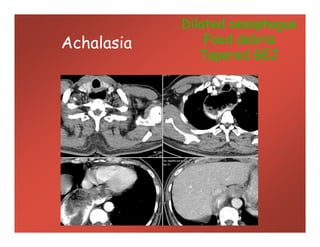

Achalasia

Dilated oesophagus

Food debris

Tapered GEJ